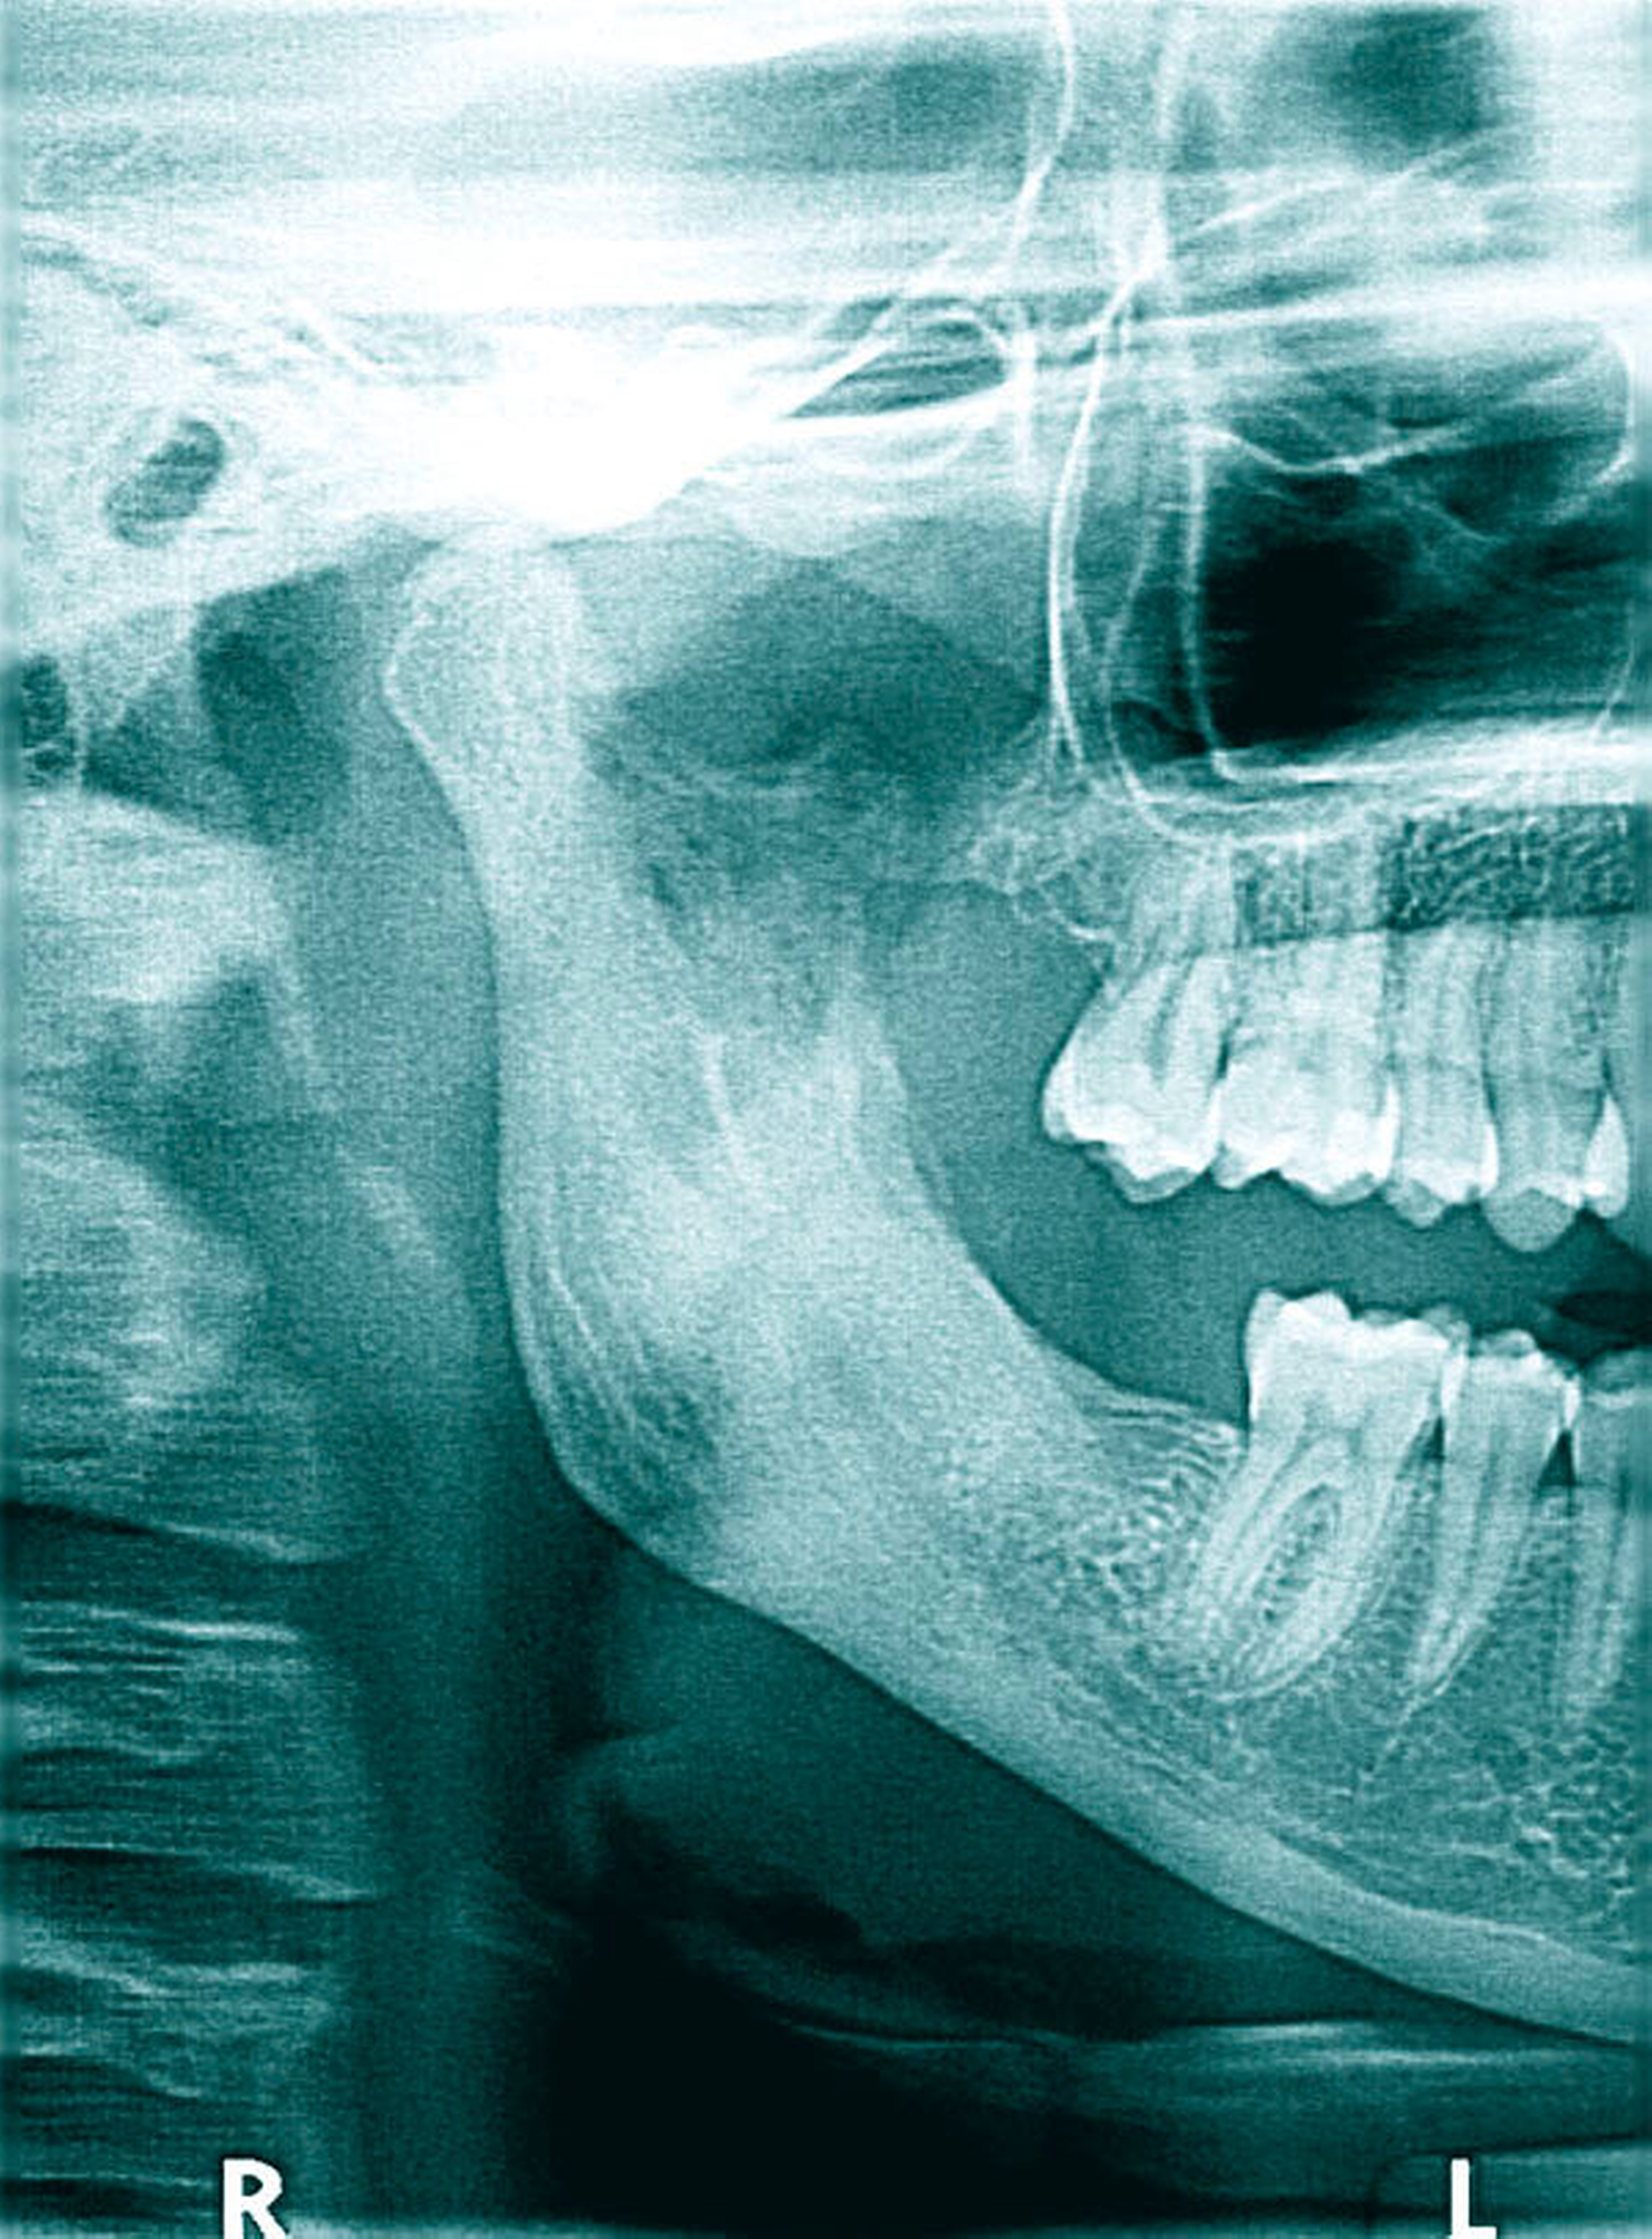

Fünf Monate später wurde die Patientin mit rezidivierenden Wundproblemen in Regio 048 und Zustand nach Wundrevision beim Zahnarzt erneut vorstellig. Ein nun von uns erstelltes Halbseiten-OPG (Abbildung 2) zeigte einen periapikal verbreiterten PA-Spalt des Zahns 47 und eine leere, unscharf begrenzte Extraktionsalveole Regio 048. Wir führten eine erneute ambulante Wundrevision und plastische Deckung durch und rezeptierten ein orales Analgetikum (Novalgin) und ein orales Antibiotikum (Clindamycin). Eine Ultraschalluntersuchung erbrachte lediglich den Verdacht auf reaktive Lymphknoten unterhalb des rechten Kieferwinkels jugulo-digastrisch.